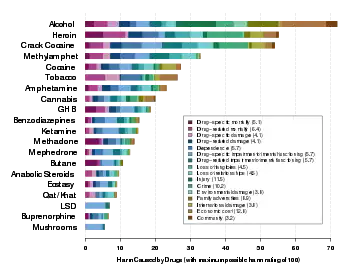

Cannabis dependence develops in about 9% of users, significantly less than that of heroin, cocaine, alcohol, and prescribed anxiolytics,[13] but slightly higher than that for psilocybin, mescaline, or LSD.[14] Of those who use cannabis daily, 10–20% develop dependence.[15]